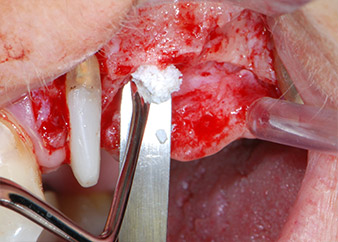

Antes de colocar el implante, el tejido infectado del hueso alveolar ubicado en el lugar del implante y alrededor de los dientes del pilar se retiró con un inserto concebido en un principio para modelar huesos y recoger virutas óseas: Piezomed y el inserto B5 (figuras 6 y 7).

En el siguiente paso, los lechos del implante se prepararon en las posiciones 25 y 26 con instrumentos rotatorios, utilizando un contra-ángulo con un coeficiente de transmisión de 20:1 (WS-75 L, W&H), junto con el nuevo potente motor de implantes Implantmed de W&H (figuras 8 y 19).

La preparación final junto al seno se realizó de nuevo con un inserto piezoeléctrico (Piezomed S2).

Antes de la colocación del implante y tras la verificación de que la membrana de Schneider estaba intacta (figura 9), la base interna del seno se aumentó en las dos posiciones del implante con un material sustituto de hueso xenógeno (Bio-Oss, Geistlich Biomaterials) (figura 10).